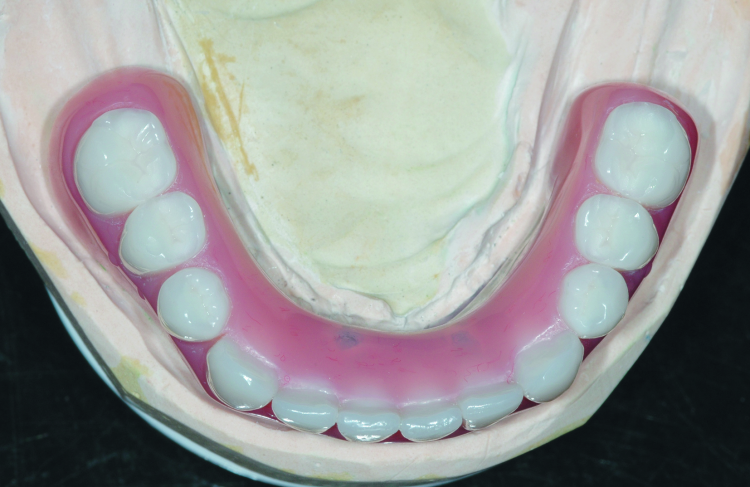

Fig. 10: Completed laboratory restoration; note the termination the arch at the first molar to avoid excessive cantilever length. The chrome frame is opaqued on the functional side to prevent gray show-through.

Fig. 11: Completed laboratory restoration showing the metal frame and recessed area to receive the SynCone caps.

The denture set-up with a final bite record were returned to the dental lab, the cast metal frame was seated on the improved dental stone cast and areas around the stone copy of the SynCone caps were blocked out prior to processing. The SynCone caps will be captured intraorally, rather than having them processed in the dental laboratory. All work was completed on the duplicate stone cast rather than the original working cast. The cast metal frame was opaqued to prevent grey show-through. The set-up was transferred to the cast with the metal frame and the dentures were processed (Figs. 10 & 11).

Because the Atlantis Conus concept results in a fully implant-supported prosthesis, the peripheral borders of the finished structure were greatly reduced and the occlusal table was abbreviated at the first molar. The length of functional arch follows the identical AP spread principles used for hybrid prosthetics to avoid excessively long cantilevers.